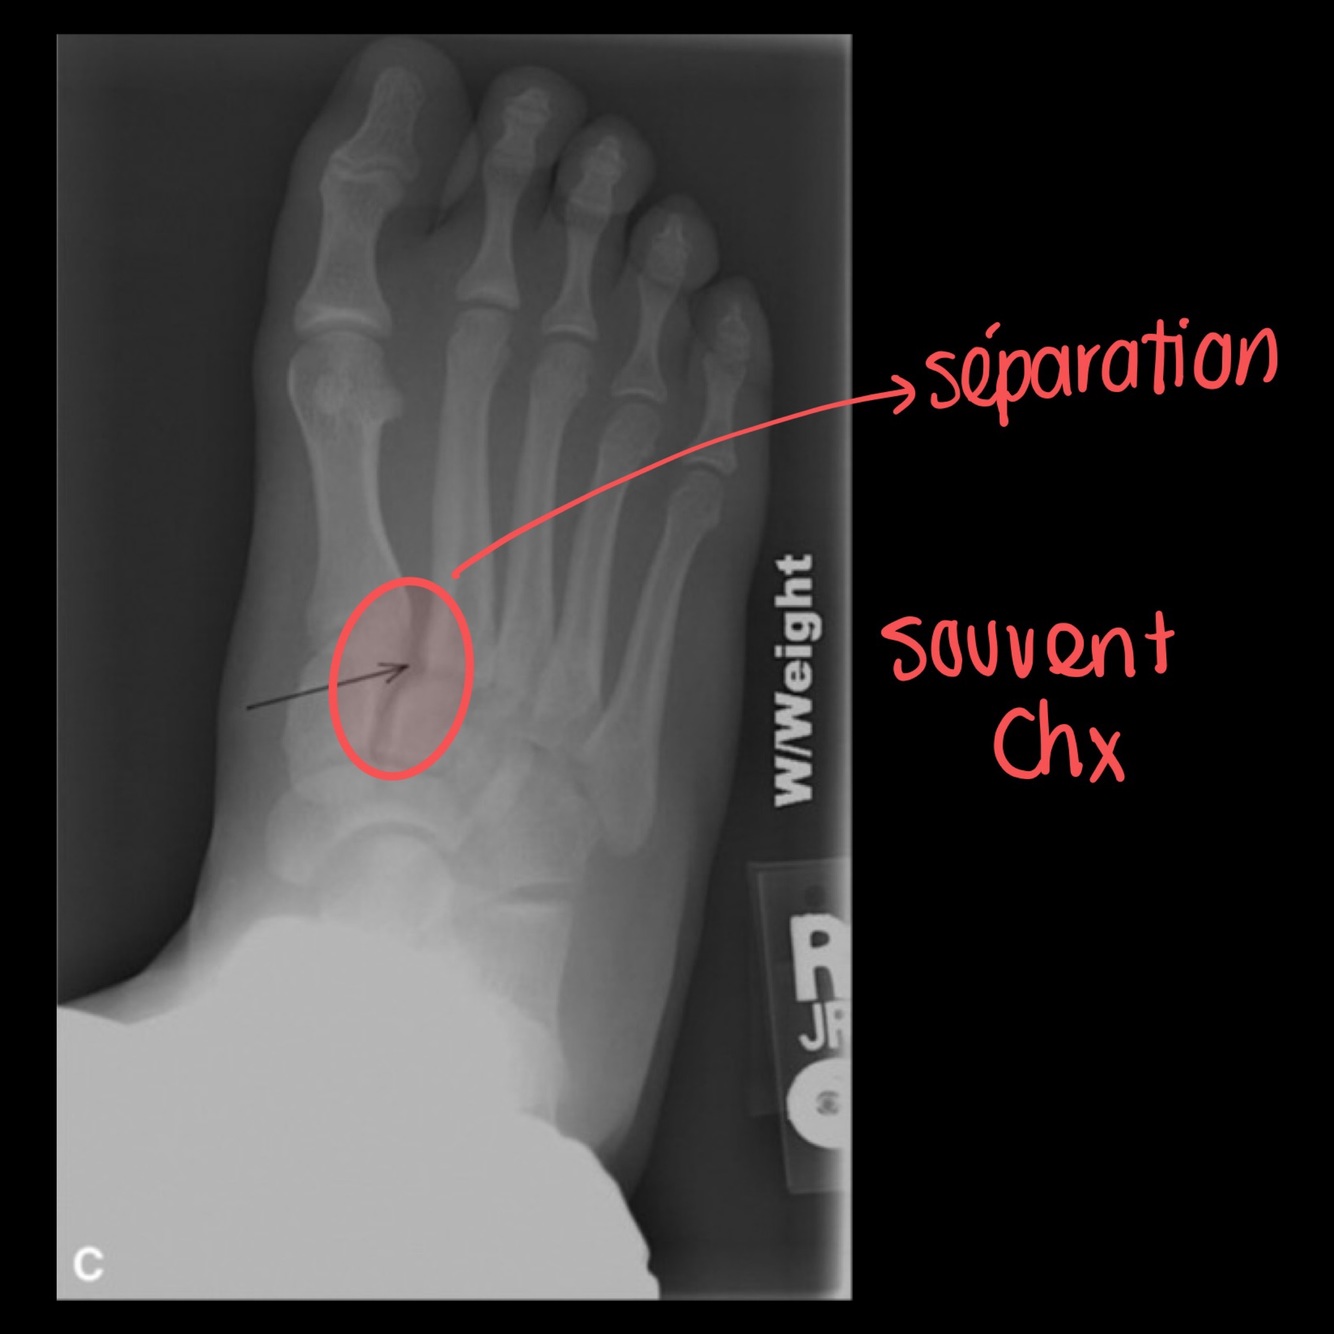

Pourquoi demander une projection en charge du pied?

A

Utile pour mettre en évidence une atteinte de Lisfranc subtile